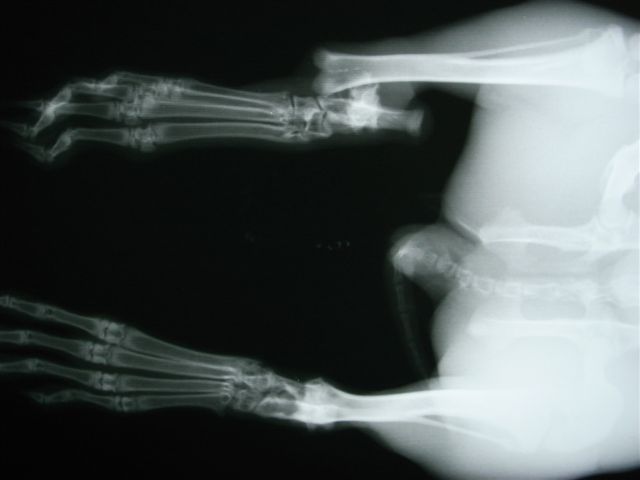

骨折する場所は太股の骨(大腿骨)、すねの骨(頸骨)、背骨(脊椎)です。後ろ足の力が強いために起こります。足の骨の場合、骨の中に金属の棒(ピンニング)やプレートで固定をして外側から固定をして、動かないようにケージに入れておきます(ケージレスト)。1ヶ月から2ヶ月ぐらいかかると思ってください。

右頚骨の骨端線で骨折。